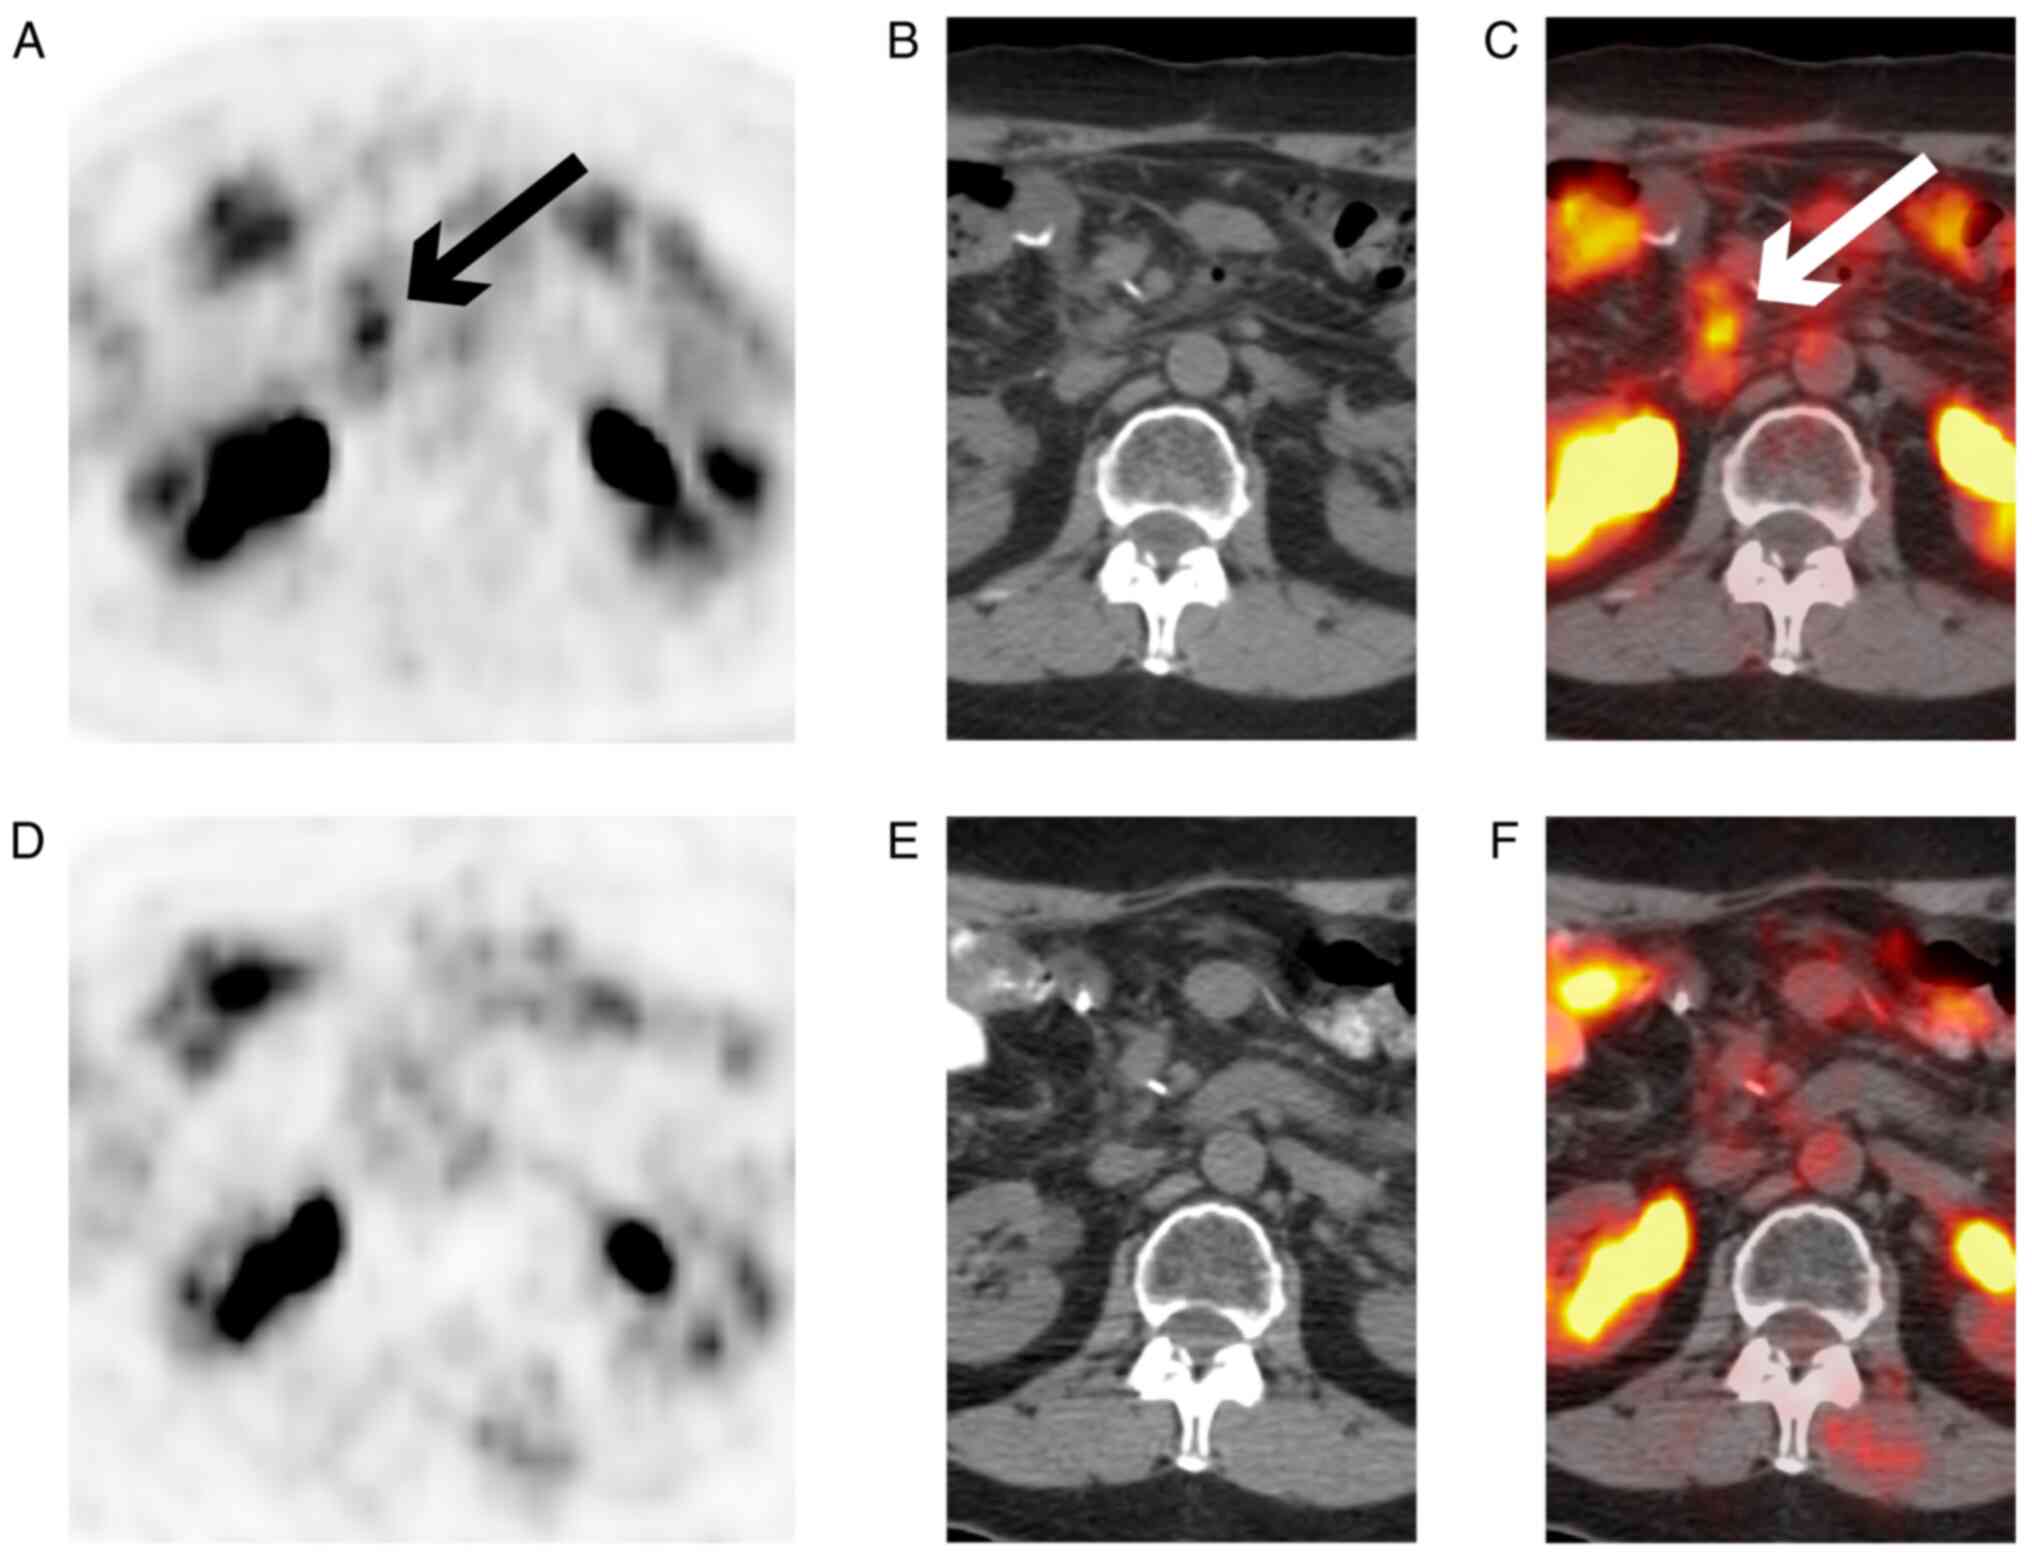

DeltaRex‑G is a replication‑incompetent amphotropic murine leukemia virus‑based retroviral vector that displays a collagen‑matrix‑targeting decapeptide on its surface envelope protein, gp70, and encodes a cytocidal ‘dominant negative’, i.e. a truncated construct of the executive cyclin G1 (CCNG1) oncogene. DeltaRex-G inhibits the CCNG1 function of promoting cell competence and survival through the commanding CCNG1/cyclin‑dependent kinase (CDK)/Myc/mouse double minute 2 homolog (Mdm2)/p53 axis. In 2009, DeltaRex-G was granted Fast Track designation from the US Food and Drug Administration for the treatment of pancreatic cancer. In 2019, the results of a phase 1/2 study that used DeltaRex-G as monotherapy for stage 4 chemotherapy-resistant pancreatic ductal adenocarcinoma (PDAC) were published. A unique participant of the aforementioned phase 1/2 study is now an 84‑year‑old Caucasian woman with chemoresistant PDAC who was treated with DeltaRex‑G, 3x1011 colony forming units (cfu)/dose, 3 times/week for 4 weeks with a 2‑week rest period, for 1.5 years. During the treatment period, the patient's tumors in the liver, lymph node and peritoneum exhibited progressive decreases in size, which were accompanied by a reduction and normalization of serum carbohydrate antigen 19‑9 levels, and the patient achieved complete remission after 8 months of DeltaRex‑G therapy with minimal side effects (grade 2 fatigue). Henceforth, the patient has been in remission for 12 years with no evidence of disease, no late therapy‑related adverse events, and no further cancer therapy following DeltaRex‑G treatment. The present study reports a mutation of tumor protein p53 (TP53) (G199V) found retrospectively in the patient's archived tumor samples. TP53 is a well‑characterized tumor suppressor gene, and a critical regulatory component of the executive CCNG1/CDK/Myc/Mdm2/p53 axis, which regulates proliferative cell competence, DNA fidelity and survival. Studies are underway to determine whether TP53 mutations in pancreatic cancer can help identify a subset of patients with advanced metastatic cancer with an otherwise poor prognosis who would respond favorably to DeltaRex‑G, which would broaden the treatment options for patients with otherwise lethal PDAC.

Figure 1

Figure 2

Figure 3

Figure 4